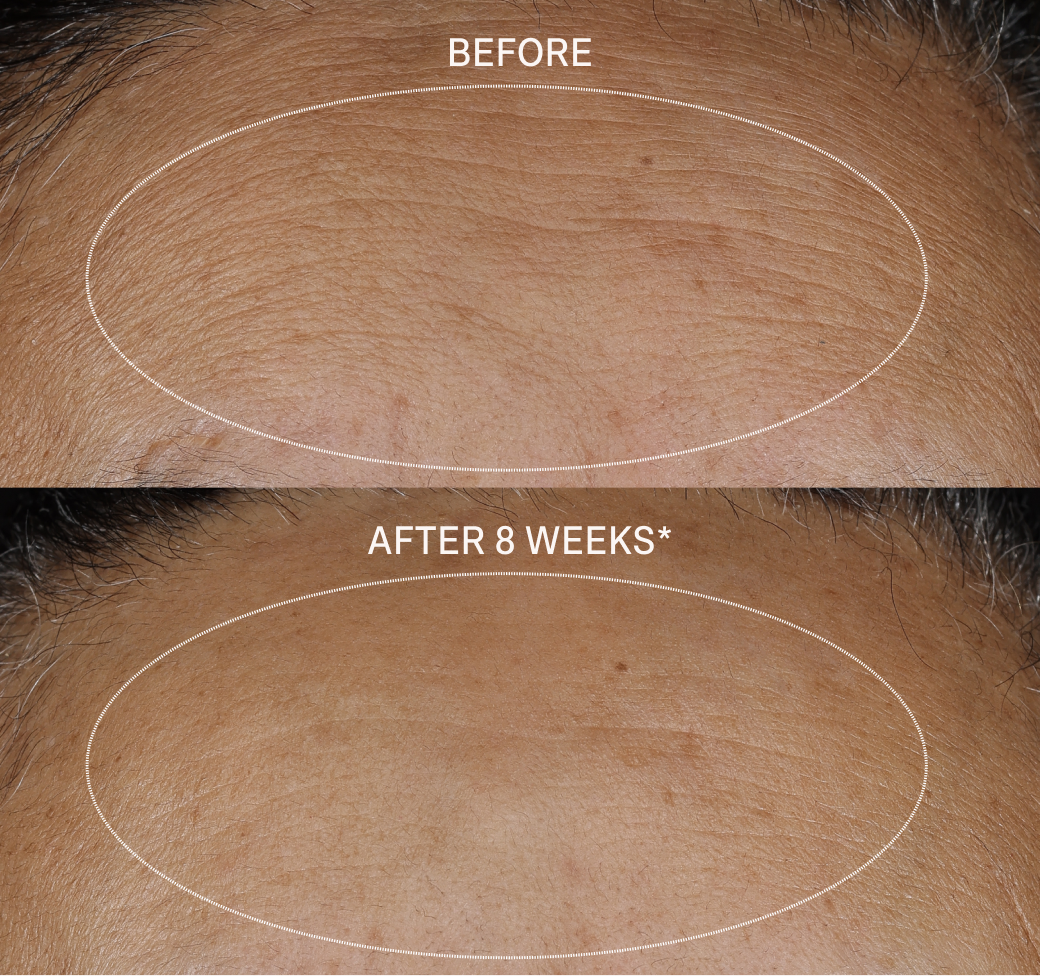

SMOOTHS AWAY FINE LINES AND WRINKLES

Decreases the breakdown of proteins in the skin to minimize fine lines and wrinkles and smooth the skin texture.

After 8 weeks*:

- 100% had firmer skin

- 100% said the overall appearance of their skin improved

- 89% saw pores appear minimized

- 89% of people said this is the best anti-aging serum they have ever used

After 8 weeks*:

- 100% had firmer skin

- 100% said the overall appearance of their skin improved

- 89% saw pores appear minimized

- 89% of people said this is the best anti-aging serum they have ever used